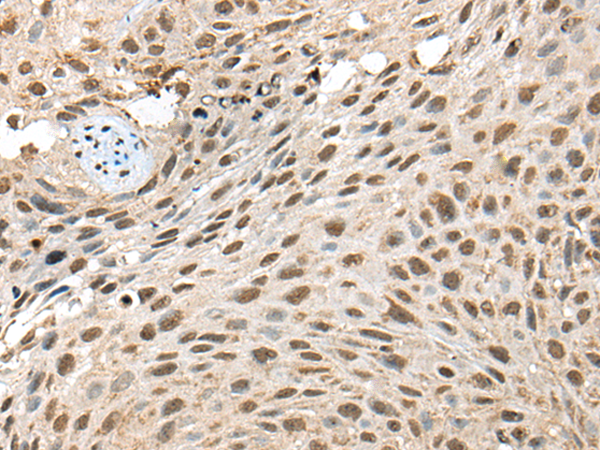

分类: 科研抗体货号: P02443别名: CT3; CT95; CTAG3; bA69L16.7应用: WB,IHC反应种属: Human